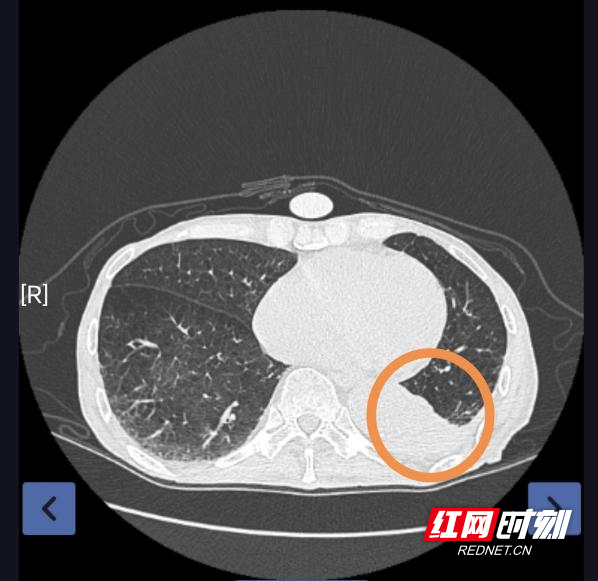

CT下左肺下叶支气管内痰栓、阻塞性肺不张

邓爷爷(化名)今年82岁,既往有慢性支气管炎、肺气肿病史,此次因受凉后反复咳嗽、胸闷、活动后气短再次入院。胸部CT提示支气管炎、肺气肿、左肺下叶支气管内痰栓及左肺下叶阻塞性肺不张,经综合内科会诊后,建议进一步行纤维支气管镜检+肺泡灌洗。但患者同时合并“脑梗死后遗症、慢性肾功能不全、肾性贫血、高血压病3级(极高危)”等多种基础疾病,肺功能及脏器储备功能明显下降。